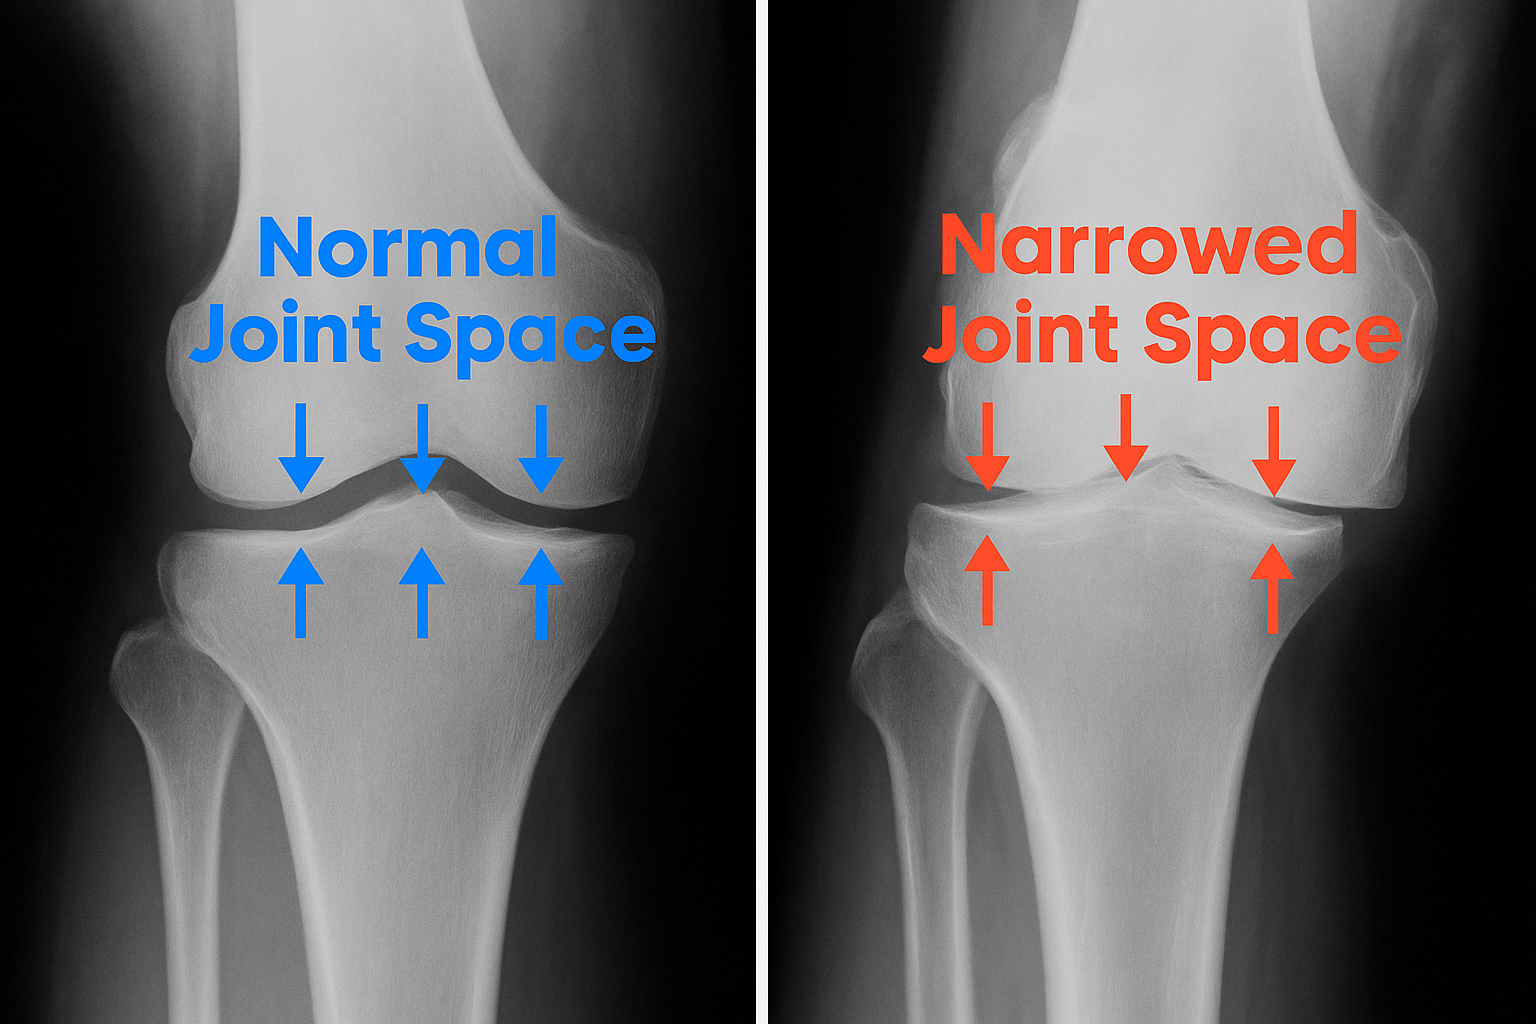

Absolutely! Alivix was specifically formulated to address issues such as worn cartilage in knees,

hips and shoulders.

Our powerful formula combines ingredients like glucosamine and MSM, which are known to rehydrate and

lubricate cartilage. These ingredients work together to help rebuild cartilage — like a protective

Teflon coating for your joints — reducing friction and promoting smoother movement.